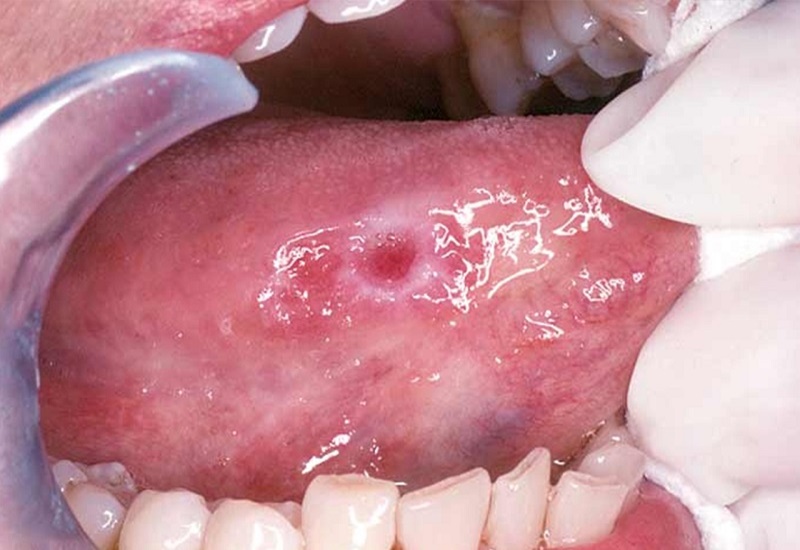

Ung thư miệng xuất hiện khi các tế bào bất thường trong niêm mạc má, lợi, vòm miệng, lưỡi hoặc môi tăng sinh không kiểm soát được và có khả năng di căn, xâm lấn sang khu vực xung quanh. Đây là một loại ung thư vùng đầu – cổ.

• Ung thư lưỡi

• Màu sắc niêm mạc thay đổi: Theo hướng nhợt màu hoặc đen lại. Một số trường hợp niêm mạc miệng trở nên dày, xơ cứng và thô hơn, có ban trắng bợt hoặc đỏ thì đó là sự cảnh báo ung thư đã biến chứng.

• Vết loét kéo dài không khỏi: Miệng sẽ có xuất hiện vết loét kéo dài hơn 2 tuần mà mãi không có dấu hiệu khỏi, kèm theo đó là cảm giác nóng rát, đau đớn.